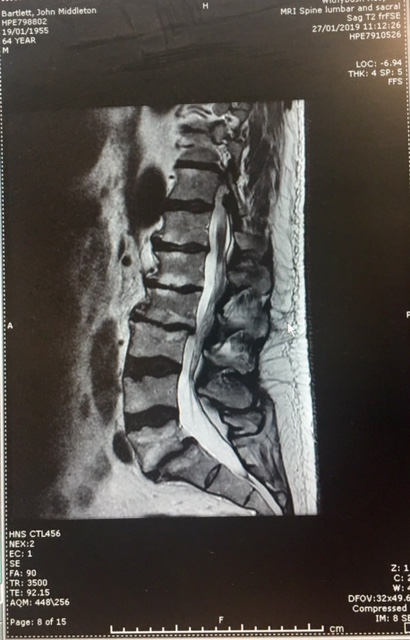

Just one mind boggling ruling was Judge McRae’s refusal to allow the Spinal Surgeon time to give his full evidence in the Witness Box JB – 26, or even to show the Jury the all important x-rays of my injuries. New MRI Images, below (New MRI Report), submitted to the CCRC in 2019 clearly showed the same accident damage the jury were prevented from seeing by my Trial Judge on 11th Nov 1994.

In 2019 this new MRI Report confirmed what the Spinal Surgeon had originally identified back in 1993:

“Both exiting nerves are flattened, more on the right side… severe narrowing of the L5 – S1 exit foramina, more on the right side, compromising the exit nerves”:

In 2023 the CCRC accepted new MRI scans[63][64] and acknowledged that Judge MacRae had wrongly curtailed important medical evidence, preventing it from being heard by my Jury. The new MRI scans confirmed multiple spinal fractures with two broken vertebrae, one having being knocked forward in my lower spine by a quarter of an inch, flattening and severely narrowing the exiting nerves to my right leg, causing a Spondylolisthesis at level L5 S1. These scans proved my injuries were caused by a serious traumatic impact, consistent with my 1988 horse riding accident and evidence the Spinal Surgeon had attempted to tell the Jury[65] but, as with so many cases submitted to the CCRC, they failed to do anymore than a simple desktop Case review. They refused to investigate the inaccurate police timeline and refused to interview witnesses and declined to refer my Case back to The Court of Appeal.